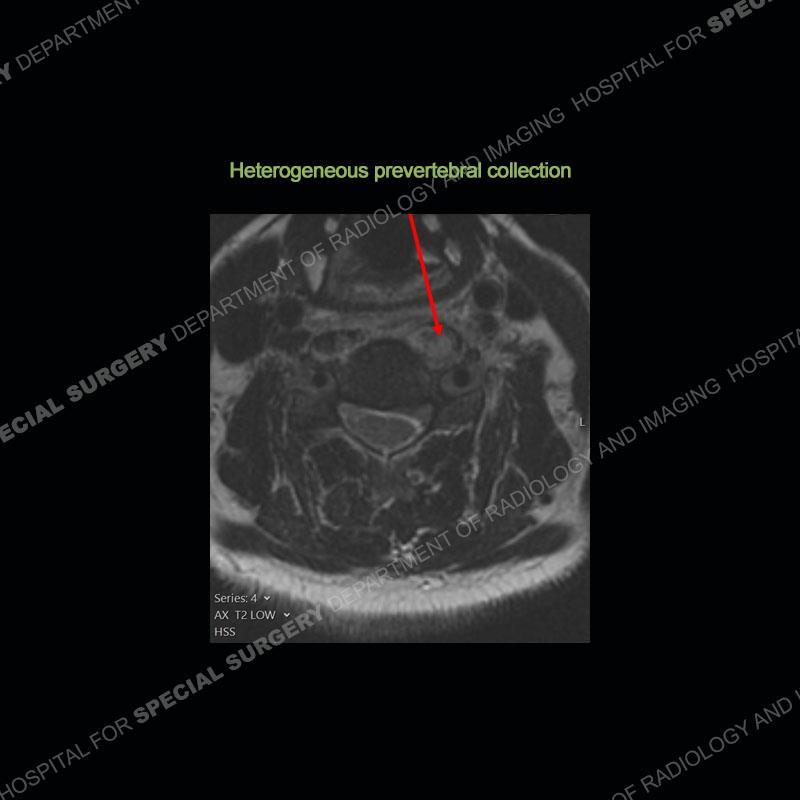

The radiographs demonstrate a prevertebral soft tissue fullness centered at C5-C6 that persists even on extension. There is a slight loss of disc height at C5-C6. The CT more readily shows the prevertebral soft tissue swelling at C5C6 where there is a punctate focus of gas. On the MRI, there is a marked amount of edema and a heterogeneous collection in the prevertebral soft tissue at C5-C6. Edema is present of the C5 and C6 vertebral bodies with a loss of the normal architecture about the disc space. A heterogeneous epidural collection has formed that causes compression of the spinal cord asymmetric to the left side and also precipitates severe left sided neural foraminal stenosis.